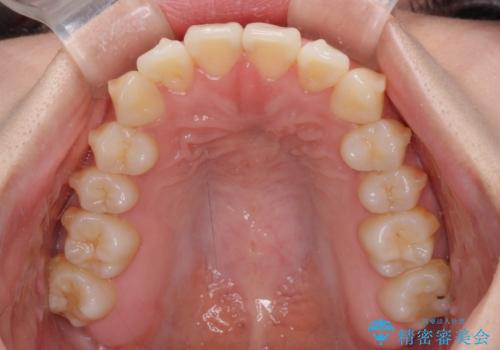

- 前歯のクロスバイトが気になり、インビザラインによる矯正治療を希望して来院された患者様です。

上顎側切歯(上の真ん中から2番目の歯)が舌側転位している場合、インビザラインでは仕上げきれないことが多く、更には無理して動かそうとすると歯髄壊死を起こすリスクが高いと言われています。

インビザラインで歯列を移動する前に、上顎前歯をワイヤー矯正で整え、その後上下歯列をインビザラインにて矯正治療を行うこととしました。

舌側転位している側切歯特有の、切縁の位置が不揃いであったり、根元が内側に引っ込んだ状態であったりという、インビザライン独特の仕上がりになることなく、きれいに整った歯列とすることができました。